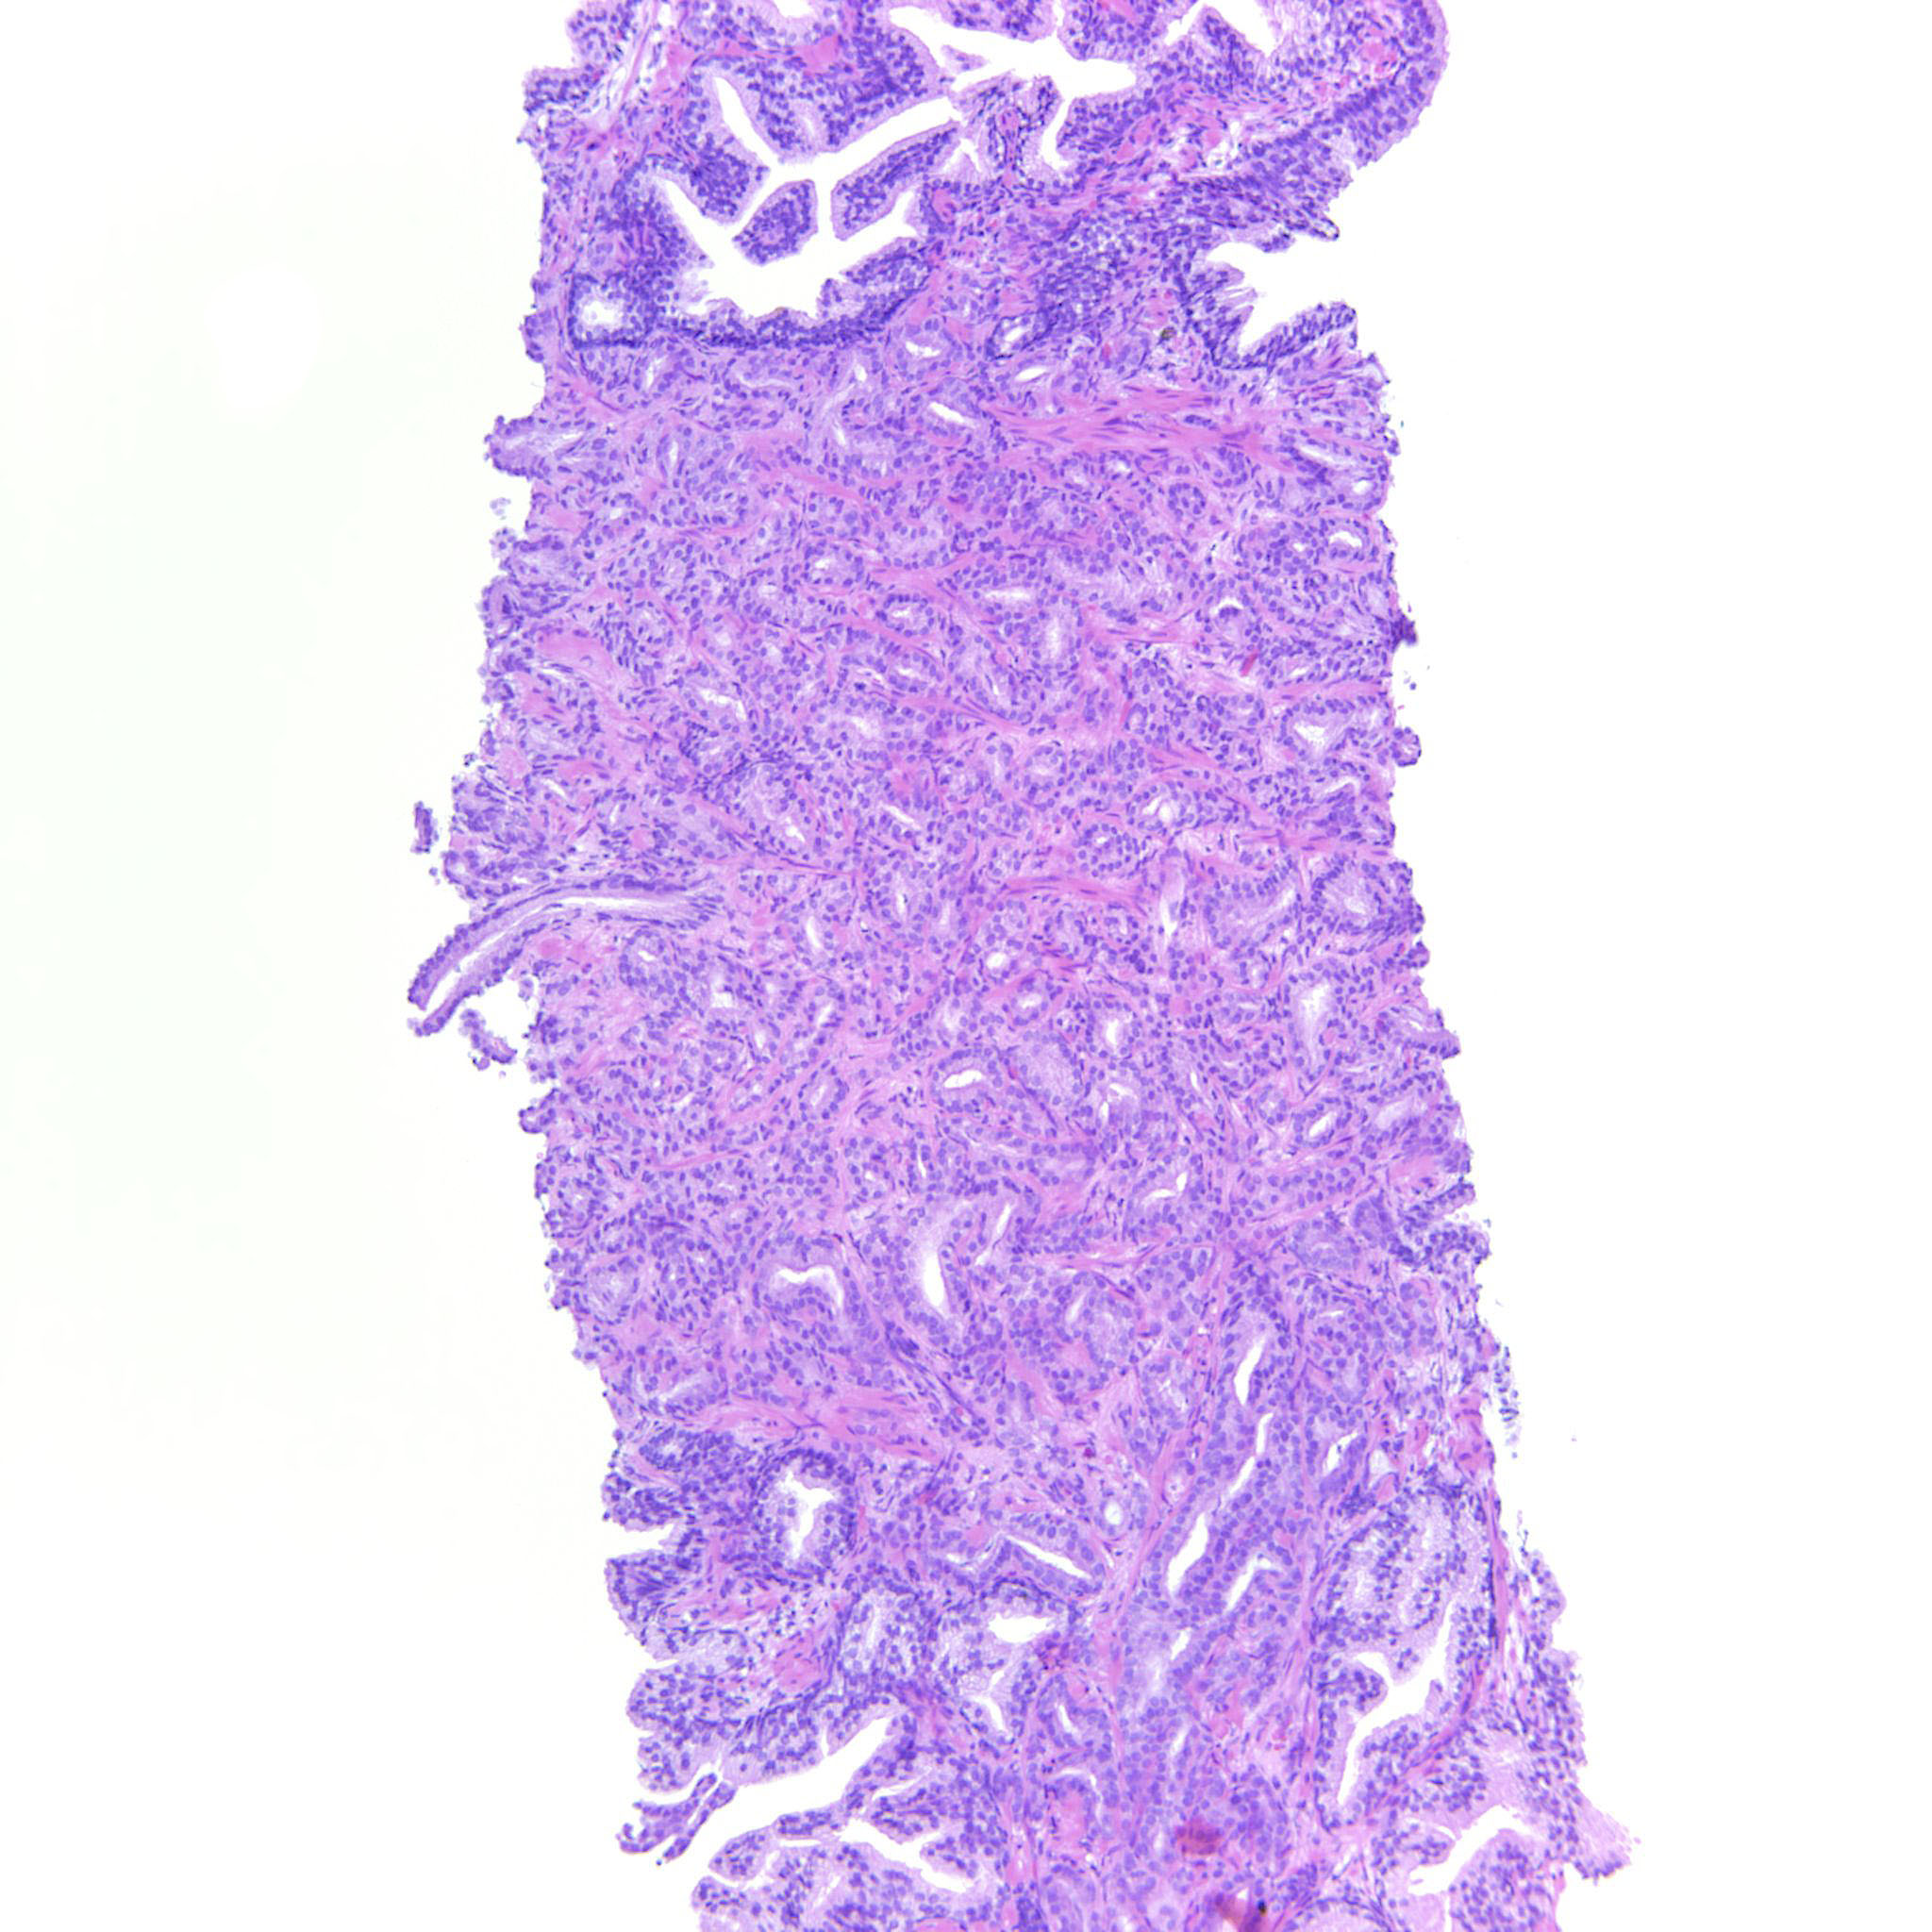

Consensus grade: GS 3+4=7 (ISUP 2)

Case description (by case creator):

Some images only contain GP3 but there are also areas with poorly formed and fused glands justifying 347.